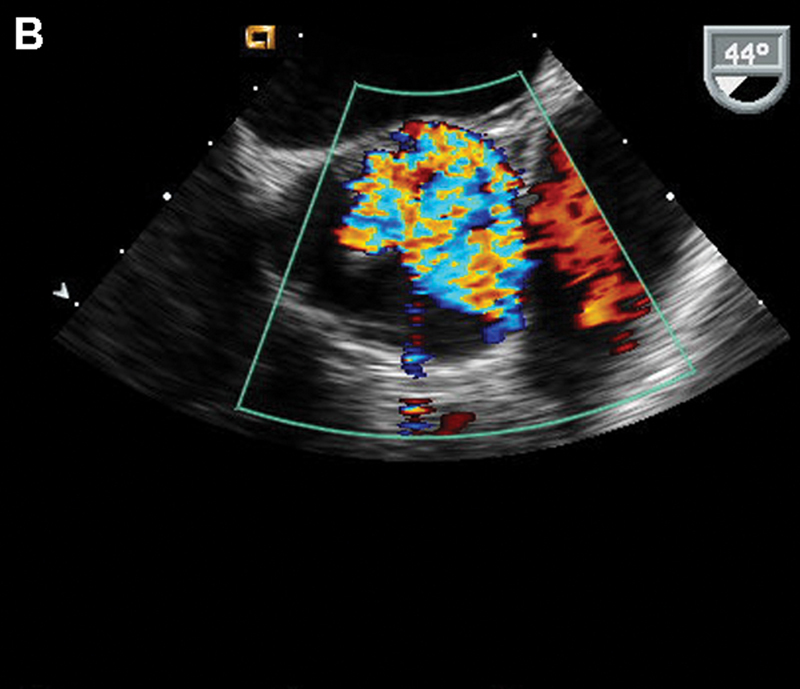

فحوصات تشخيصية لبعض امراض القلب والشرايين التاجية